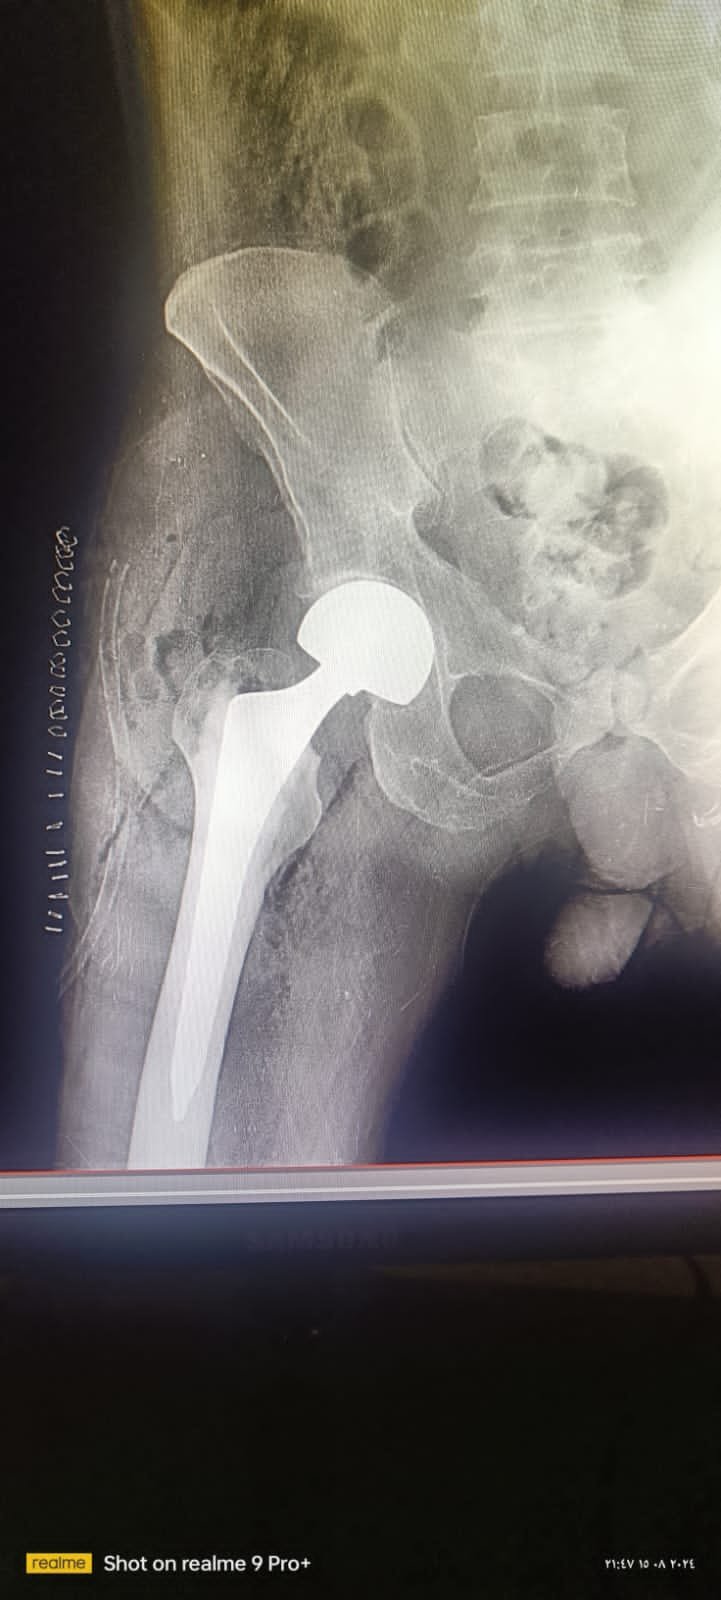

تتضمن العملية استبدال الأجزاء التالفة من مفصل الحوض بأجزاء صناعية مصنوعة من مواد متينة مثل البلاستيك والمعدن. هذه الأجزاء مصممة لتحاكي حركة المفصل الطبيعي قدر الإمكان، وتتمتع بعمر طويل يسمح للمريض بالاستفادة منها لسنوات عديدة. نسبة نجاح عملية تغيير مفصل الحوض تعتمد على عدة عوامل تشمل حالة المريض الصحية، وخبرة دكتور العظام تخصص مفصل الحوض، ومتابعة ما بعد العملية.يوجد عدة خيارات لكل جزء من هذه الاجزاء مما قد يؤثر علي سعر عملية تغيير مفصل الحوض.

عامل آخر مهم هو نوع المفصل الصناعي المستخدم في العملية. توجد أنواع مختلفة من مفاصل الحوض الصناعية،بالنسبة لجزء الرأس فهناك عدة خيارات تتفاوت في الجودة والمواد المستخدمة، مثل الرأس المعدني والرأس السيراميكي .و أيضا هناك أنواع للجزء الذي يحتك برأس عظمة الفخذ فهي اما من بلاستيك عالي الترابط مغذي بفيتامين أ او تكون معدنية او سيراميكية ايضا.المفاصل المصنوعة من مواد عالية الجودة والمصممة بواسطة تقنيات متقدمة عادة ما تكون ذات تكلفة أعلى، ولكنها توفر أداءً أفضل وعمر افتراضي أطول.

يتم بعد ذلك إعداد وتجهيز المنطقة لتلقي المفصل الصناعي الجديد. يُعتمد في هذا الإجراء على تقنيات متقدمة مثل استخدام الأشعة السينية لضمان وضع المفصل الجديد بدقة تامة. يتم اختيار المفصل الصناعي بعناية ليتناسب مع تشريح وحجم عظم المريض، مما يساهم في تحقيق نتائج أفضل وضمان استقرار المفصل على المدى الطويل.

يتم تثبيت المفصل الصناعي بأحد الطريقتين: إما باستخدام الأسمنت العظمي الخاص أو بطرق غير أسمنتية تعتمد على تصميم المفصل نفسه لتحفيز نمو العظم حوله وتثبيته طبيعياً. يعتمد اختيار الطريقة على عدة عوامل منها عمر المريض ونوع وجودة العظام.